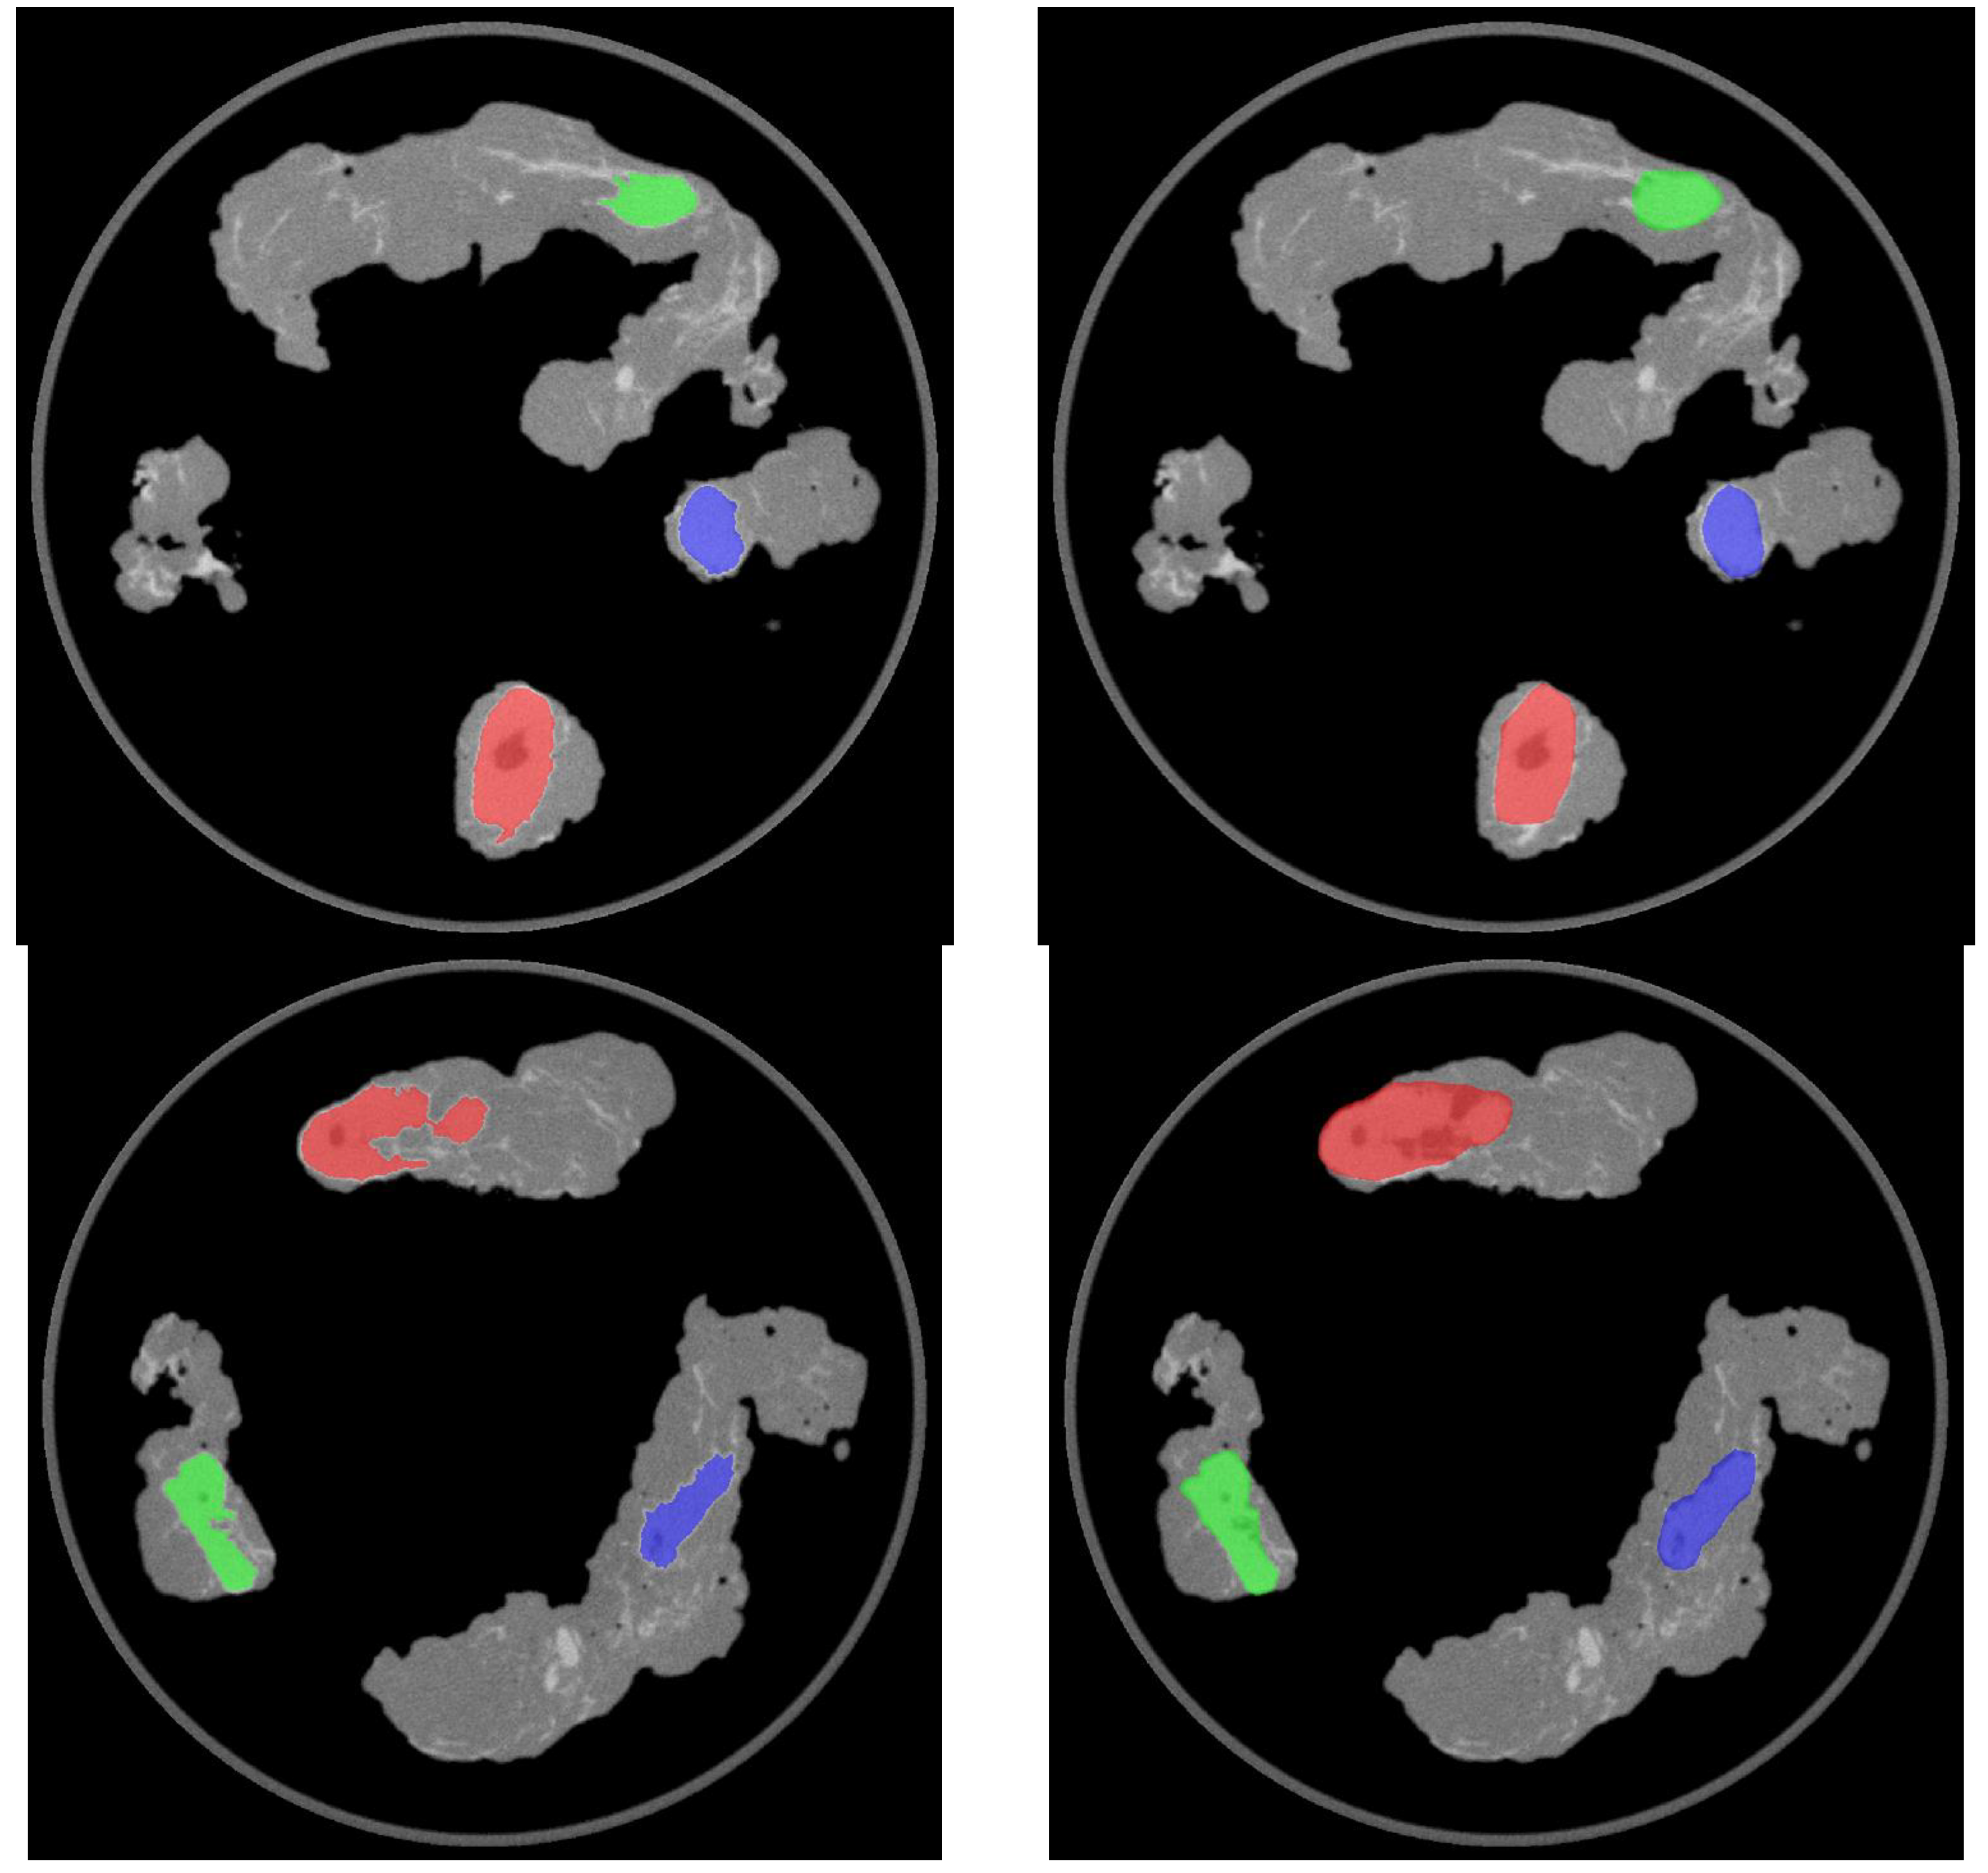

| Left Pelvic Lymph Nodes | SUVmax | Target-to-Background Ratio (TBR) | Lymph Node Histopathology |

| Left proximal external iliac | 5.9 | 3.5 | Negative |

| Left obturator (1) | 6.2 | 3.7 | Negative |

| Left obturator (2) | 9.0 | 5.3 | Negative |

| Right pelvic lymph nodes | SUVmax | Target-to-background Ratio (TBR) | Lymph node histopathology |

| Right distal external iliac | 7.8 | 4.2 | Negative |

| Right proximal external iliac | 4.4 | 2.4 | Negative |

| Right obturator | 7.0 | 3.8 | Negative |